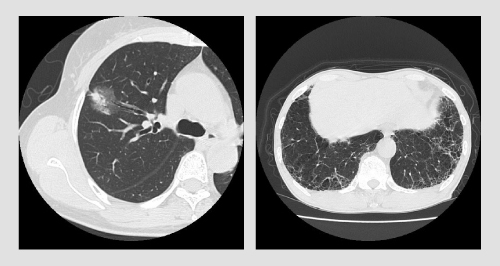

健康診断などで実施される通常のX線検査では、20mmくらいにならないとなかなか発見できませんが、マルチスライスCTによる検査なら、数ミリ単位(10mm以下)での肺がん発見が可能で、この段階であればほぼ治癒が可能とされています。

また、肺がんのほか、肺気腫、炎症など、肺や周辺部のさまざまな疾病の発見が可能です。